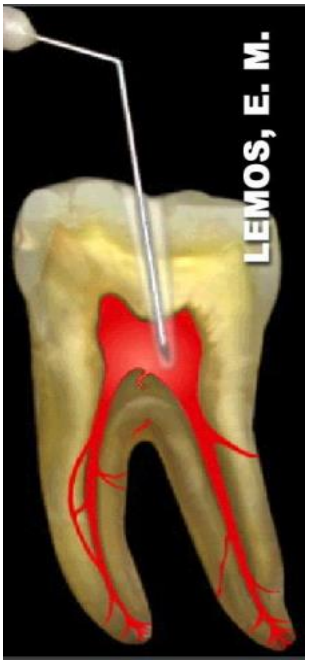

Observe a imagem abaixo:

Assinale a alternativa que apresenta o nome da técnica anestésica ilustrada na imagem: